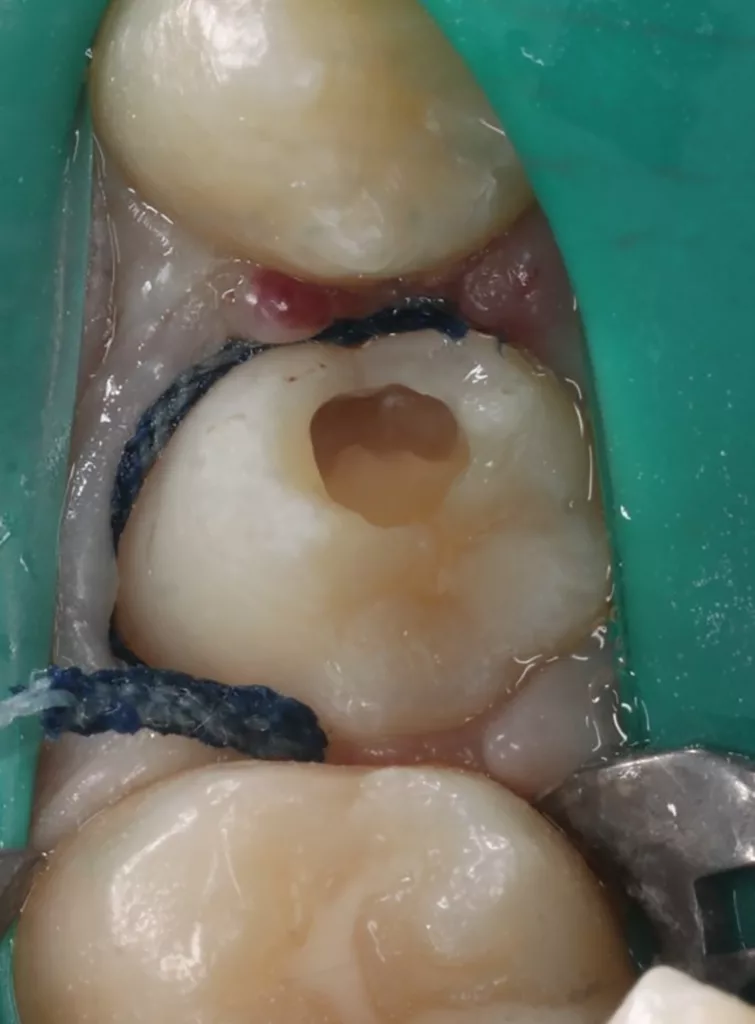

Das siebenjährige Mädchen wurde von einer Kollegin zur Behandlung einer atypischen intrakoronalen Aufhellung im Kronenbereich des nach Durchbruch befindlichen symptomatischen Zahnes 46 überwiesen (Abb. 20). Anamnestisch bestanden seit zwei Tagen kurzintervallige Spontan- und Nachtschmerzen, die mit Ibuprofen 40 mg/ml Kindersirup behandelt wurden. Das Röntgenbild zeigte einen umfangreichen runden Dentindefekt unter intaktem Zahnschmelz, der bis in das Pulpakavum reichte. Daraus ergab sich die Verdachtsdiagnose PEIR des Zahnes 46 (Grad 3 der Läsion nach Seow) in Kombination mit einer akuten Pulpitis. Nach Leitungsanästhesie am Foramen mandibulae mit Septanest 1/100 000 (Septodont, Frankreich) und STA-System (Milstone Scientific, USA) konnte der Zahn mithilfe von Kofferdam (Klammer U67, KSK Dentech, Japan) gut isoliert werden (Abb. 21). Um die ursprüngliche Zahnanatomie zu imitieren, wurde ein Okklusalstempel aus dem flüssigen Kofferdam OpalDam (Ultradent, Frankreich) und einem Microbrushapplikator angefertigt.

Der PEIR-Defekt schimmerte unter der lingualen Querfissur deutlich dunkler durch (Abb. 21), sodass die Entscheidung getroffen wurde, den Defekt an genau dieser Stelle zu eröffnen (Abb. 22). Das resorbierte intrakoronale Weichgewebe, das die Läsion nur zum Teil füllte, konnte dann gut visualisiert werden (Abb. 22). Kariös verändertes Dentin wurde nicht gefunden. Nach Eröffnung des Pulpahorns sah die Pulpa blass und avaskulär mit Anzeichen einer geringen Blutung aus (Abb. 23). Die komplette Kronenpulpa wurde bis zur Höhe der Kanaleingänge mit einem runden Diamantbohrer unter Wasserkühlung entfernt. Vor und nach der Prozedur wurde die Läsion zuerst mit 1%igem NaOCl und anschließend mit physiologischer Kochsalzlösung gespült. Die Blutung stoppte innerhalb von zwei Minuten vollständig, die Wurzelpulpa erschien gesund, regulär vaskularisiert und sauber (Abb. 24). Es wurde eine reversible Pulpitis diagnostiziert. Die Abdeckung der Wurzelpulpa erfolgte mit einem hydraulischen Kalziumsilikatzement (Rootdent, Technodent), der mit dem Glasionomerzement Fuji II LC (GC, Japan) als temporäre Füllung abgedeckt wurde. Die Platzierung des MTA-Zements wurde abschließend mittels einer Röntgenaufnahme überprüft (Abb. 27). Nach zwei Wochen war die junge Patientin komplett beschwerdefrei. Unter erneuter Trockenlegung mit Kofferdam wurde die adhäsive koronale Restauration mit Komposit Estelite ASTERIA OCE, A2B und Universal Flow AO2 (Tokuyama, Japan) mithilfe eines vorab angefertigten Okklusalstempels erstellt (Abb. 25 und 26). Ein Jahr später kam die Patientin beschwerdefrei zur Nachkontrolle. Das Röntgenbild (Abb. 28) zeigte keinen pathologischen Befund sowie eine physiologische Weiterentwicklung des Wurzelwachstums in Länge und Dicke der Wurzelwände.